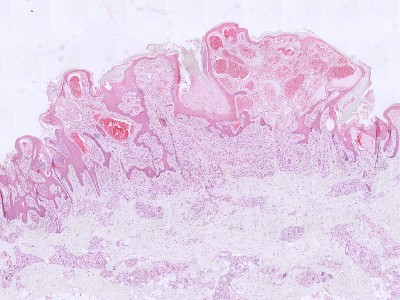

PA:Afwijkende clusters van

misvormde venule-achtige vaten

in de diepe dermis en subcutis, in combinatie met reactieve epidermale acanthose,

papillomatose, en hyperkeratose. Positief voor GLUT-1 (glucose transporter type-1)

en WT1 (Wilms tumor-1). GLUT-1 wordt vaak gezien in vasculaire tumoren.

![Histologie verruceus hemangioom (click on photo to enlarge) [source: Kevin Kwee / Afdeling Pathologie MUMC] Histologie verruceus hemangioom](../../../pacoupes/thumbnails/verruceus-hemangioom-1.jpg) |

![Histologie verruceus hemangioom (click on photo to enlarge) [source: Kevin Kwee / Afdeling Pathologie MUMC] Histologie verruceus hemangioom](../../../pacoupes/thumbnails/verruceus-hemangioom-2.jpg) |

ingescande coupe (zoom) |

Bron

hoge resolutie PA-foto's: Kevin Kwee en Afdeling Pathologie MUMC. Klik

op de afbeelding om in te zoomen.